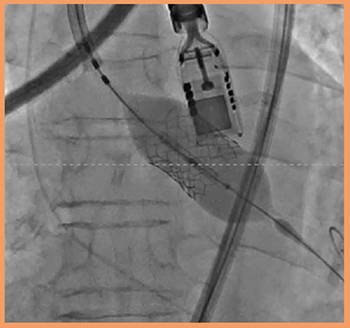

PEI-512VXは,マトリックスアレイ技術を採用し,短時間で高解像度のボリュームデータを取得可能な3D経食道プローブである(図3)。挿入性に優れた先端部形状と,把持しやすい操作部形状が特長である。また,X線が透ける素材を使用しているので,治療用のデバイスとプローブの先端が重なったとしても,ストレスなく手技を実施することが可能である(図4)。

図4 TAVI中のPEI-512VXのX線像

(画像ご提供:聖マリアンナ医科大学・出雲昌樹先生)